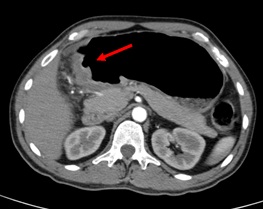

Computed Tomography Scan (CT-scan)

Endoscopic Ultrasound

Diagnostic Laparoscopic - Peritoneal Metastasis from Stomach Cancer